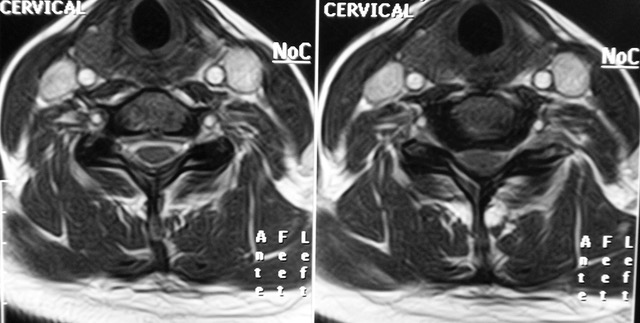

Mielopatía Cervical por Cervicoartrosis (MEC)

por Dr. Carlos Botella-Asuncion | Nov 25, 2025 | Mielopatía Cervical, Neurocirujano Valencia

La mielopatía cervical por cervicoartrosis (o mielopatía espondilótica cervical) es la causa más común de disfunción de la médula espinal en adultos mayores. Se produce debido a cambios degenerativos relacionados con la edad en la columna cervical, que incluyen...